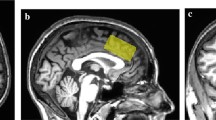

Proton magnetic resonance spectroscopy

Proton magnetic resonance spectroscopy (1H MRS) scanning took place at the Functional Magnetic Resonance Imaging of the Brain (FMRIB) Centre. Scanning was performed on a 7 T Siemens MAGNETOM scanner (Siemens, Erlangen, Germany) equipped with a Nova Medical 32 channel receive array head coil. Spectra were measured from two 8-ml voxels, one in the anterior cingulate cortex and the other in the occipital cortex (Fig. 1). Voxels were positioned manually by reference to 1-mm isotropic T1-MPRAGE image. To ensure reproducibility of voxel placement during both 1H MRS scan visits, screenshots of each anatomical region showing voxel placement in three planes were taken from each subject during the first visit. These were used to guide voxel placement during the second visit.

Voxel placement and representative spectra from the anterior cingulate cortex (ACC) and occipital cortex (OCC). Each acquired spectrum (64 averages) is overlaid with the metabolite fit from LCModel (red line) with major peaks labeled. The difference between the metabolite fit and underlying spectrum is shown below as a residual, which remains small and uniform indicating a high quality spectral fit. tCR total creatine, Ins myo-inositol, Cho choline, Glu glutamate, NAA N-acetylaspartate

The ebselen treatment was well tolerated and no participant dropped out of the study (the neuropsychological effects of ebselen treatment will be described in a separate report). MRS voxel placement and representative spectra from the anterior cingulate cortex (ACC) and occipital cortex (OCC) are shown in Fig. 1. For the ACC, we obtained 19 pairs of measurements (no measurements were obtained from one subject due to technical difficulty). Three pairs of spectra with an FWHM difference >0.01 ppm were excluded, resulting in 16 pairs being included in the analysis. For the OCC, all 20 pairs of measurements were included in the analysis. All the spectra were of high quality, with average signal to noise ratio (SNR) of 39.97 ± 1.04 (mean ± SEM), linewidth of 9.60 ± 0.34 Hz for the ACC and SNR of 45.65 ± 0.92, linewidth 9.62 ± 0.12 Hz for the OCC. All the metabolites of interest were quantified at an average CRLB of <15 %, consistent with high quality data at ultra high-field imaging.